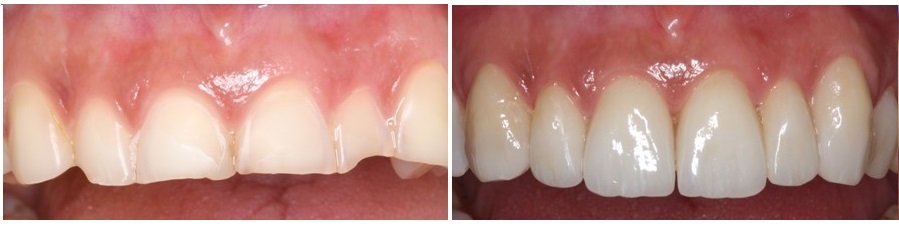

We fabricated resin veneers for the palatal side of anterior teeth and porcelain veneers for the labial side of the same teeth.

We create a sandwich, that contains the tooth itself without any further removal of tooth structure that has already happened due to the erosion.

The following picture presents the same teeth after the cementation of the palatal and labial restorations.